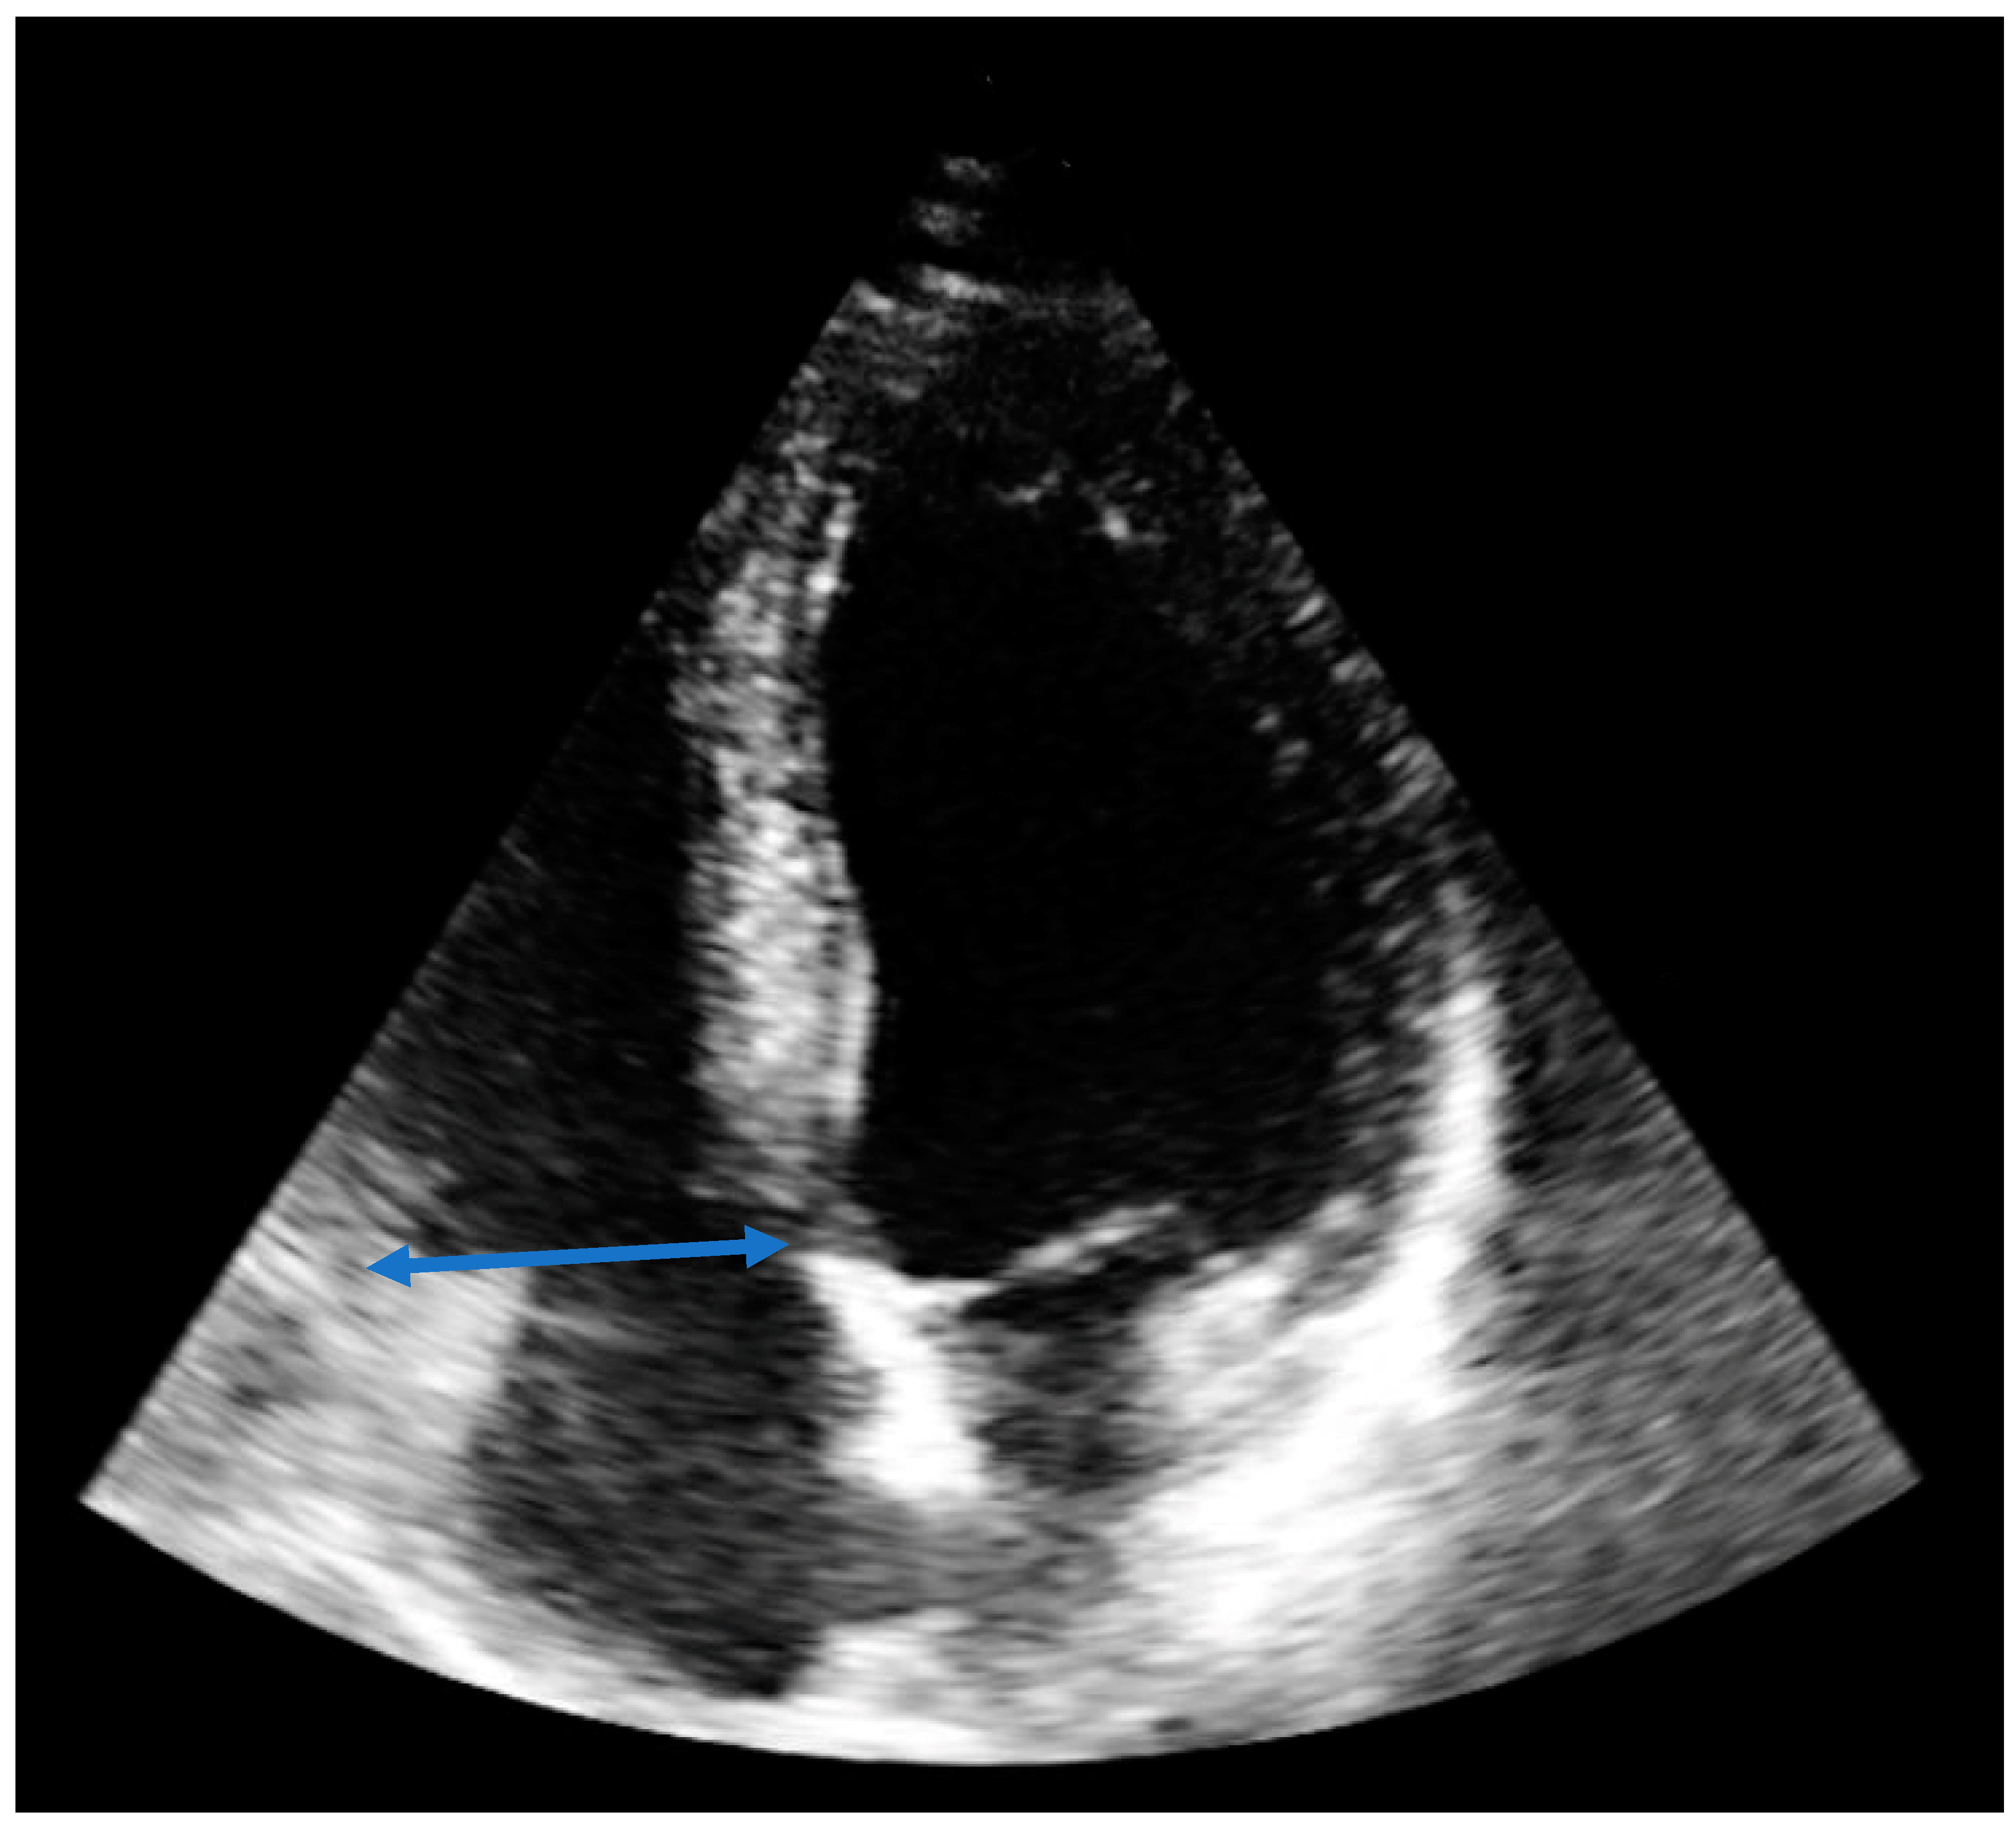

| RVEDD [mm] | 65 | 49 | 37 |

| TAPSE [mm] | 12 | 16 | 21 |

| TASV [cm/s] | 8 | 12 | 17 |

| sPAP [mmHg] | 55 | 15 | 14 |

| D- Sign | Yes | No | No |

| McConnell‘s sign | Yes | Yes | No |